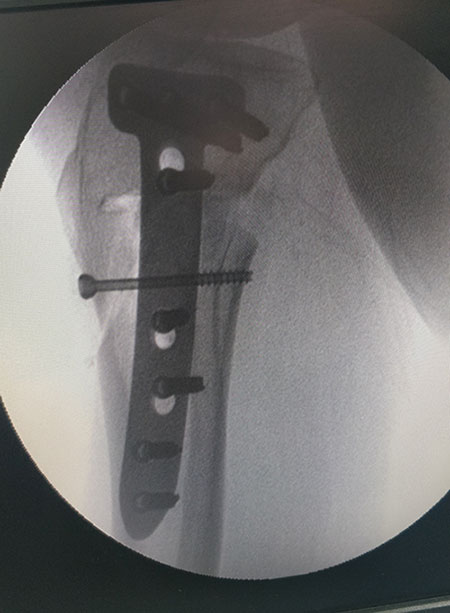

STEPS OF HTO